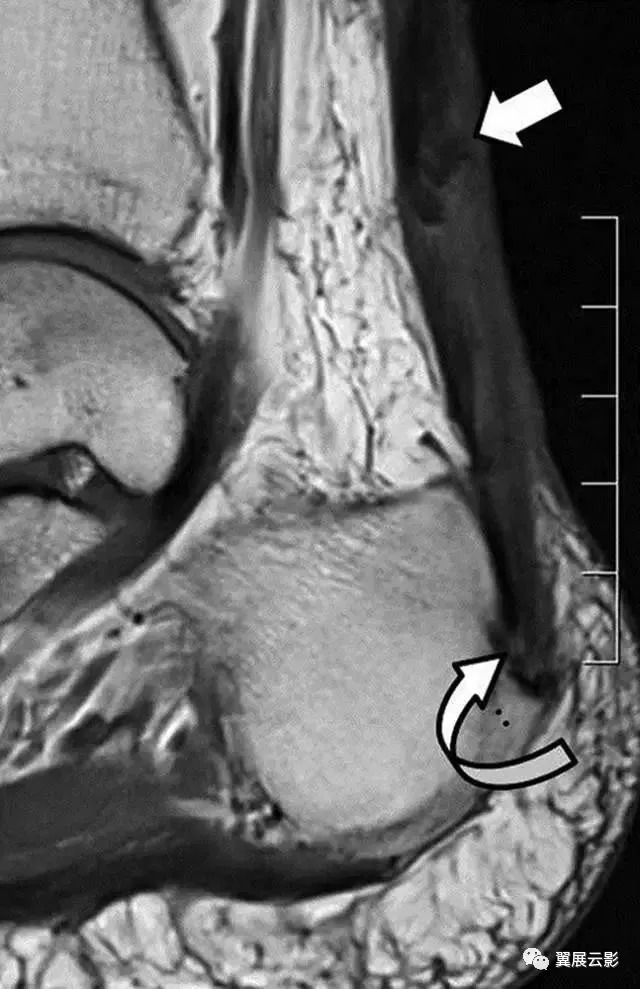

图4B-男,43岁,从马身上掉下来,经历过疼痛,踝关节背部出现瘀伤。B,损伤后6周获得的矢状T1加权MR图像显示加厚的跟腱。在腱内存在不均匀的信号强度,低信号强度的区域(直箭头)在撕脱位置上方约5cm处, 结节撕脱缺损(弯曲的箭头)。